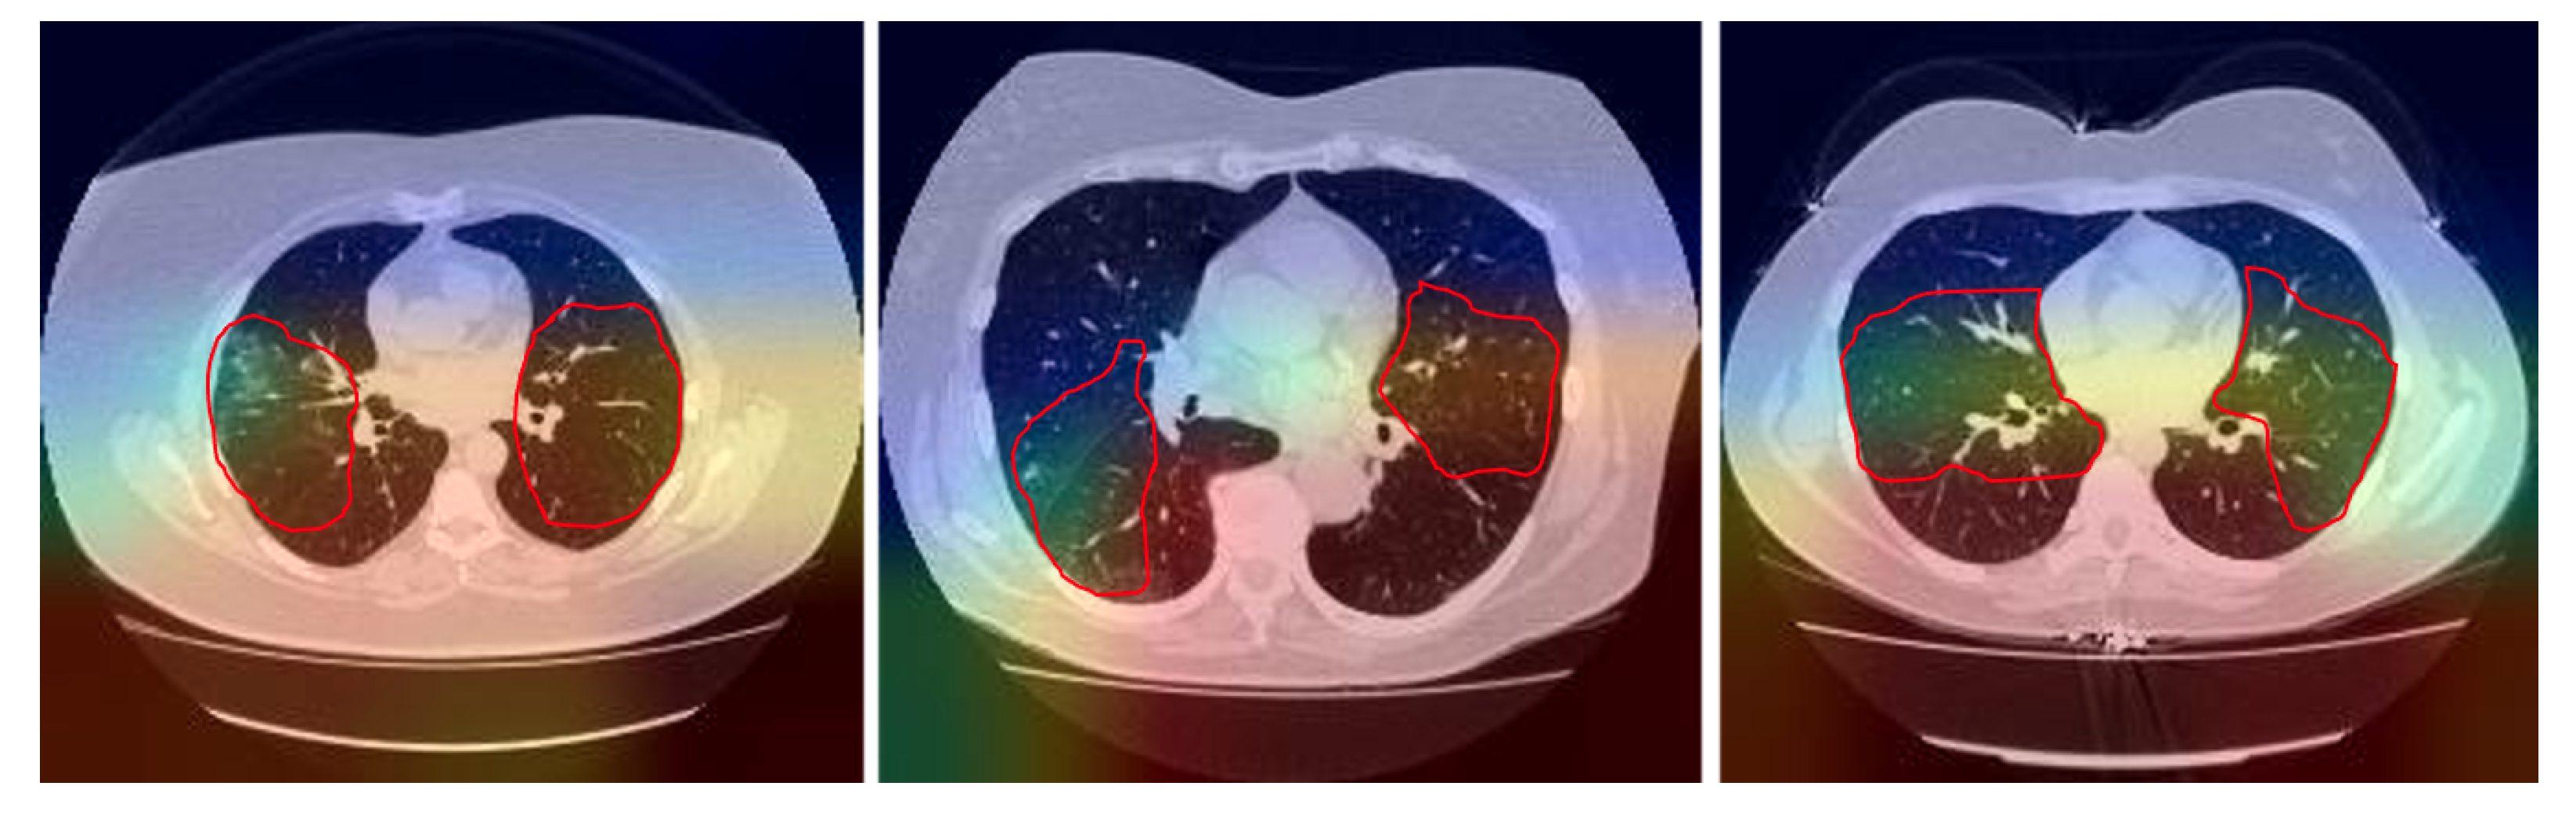

2.1. Data Preprocessing

4. Discussion